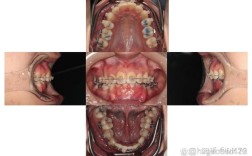

- 描述: 这是种植体周围支持组织(牙龈和牙槽骨)发生的炎症性疾病,类似于天然牙的牙周炎。牙龈萎缩是种植体周围炎最典型的表现之一,导致原本被牙龈覆盖的种植体或基台部分暴露出来。

- 牙龈萎缩,种植体或基台暴露。

- 种植体周围骨吸收(通过X光片可见)。

- 种植体末端直接暴露在口腔黏膜外: 这是最直观的表现,可以看到或摸到金属部分突出。